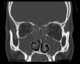

Microcornea - glaucoma - absent frontal sinuses

Absent frontal sinuses